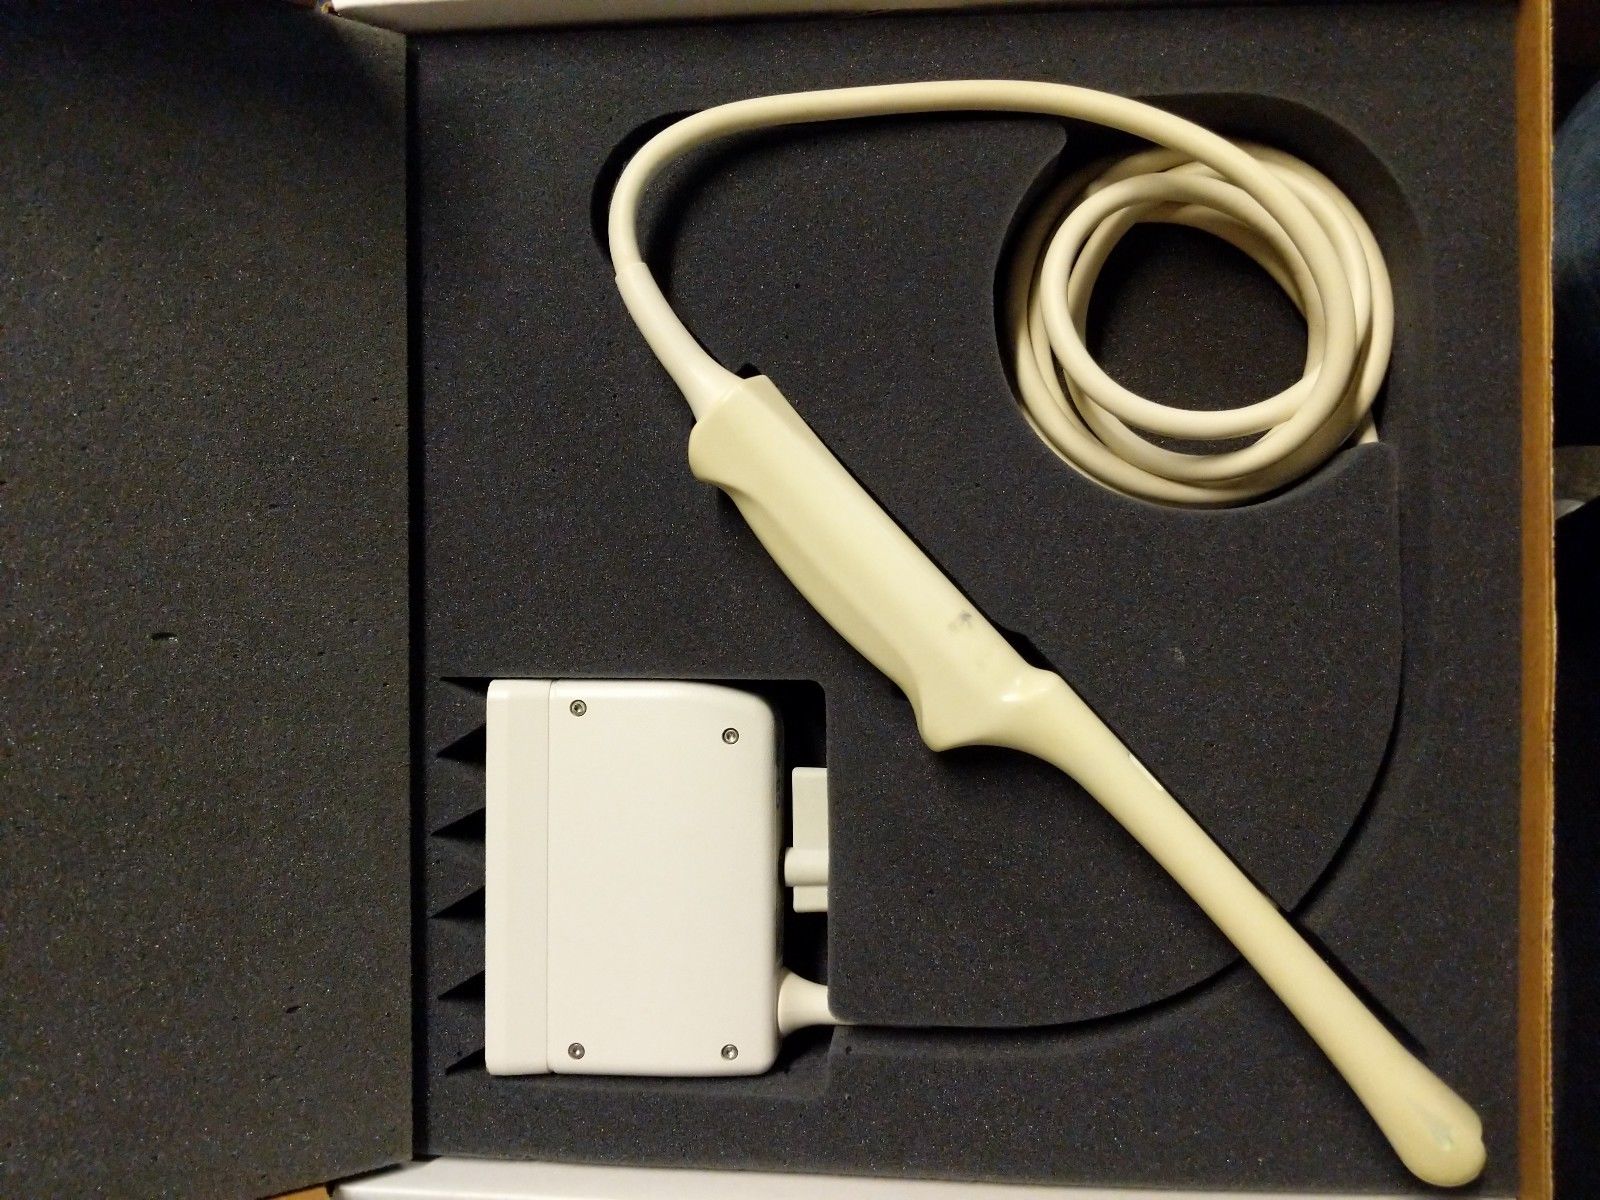

Description

ATL HDI 3500 w/ 2 Probes